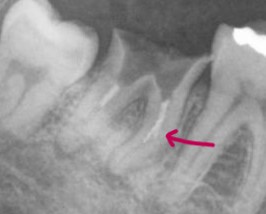

根の病気でいらした患者さんで、再治療の希望でしたが、不運なことに根管にリーマーが折れてその先の病巣への到達が困難になっています。ですが、抜歯を回避するために再根管治療で対応することになりました。

赤矢印の部分にねじねじした白いものが見えます